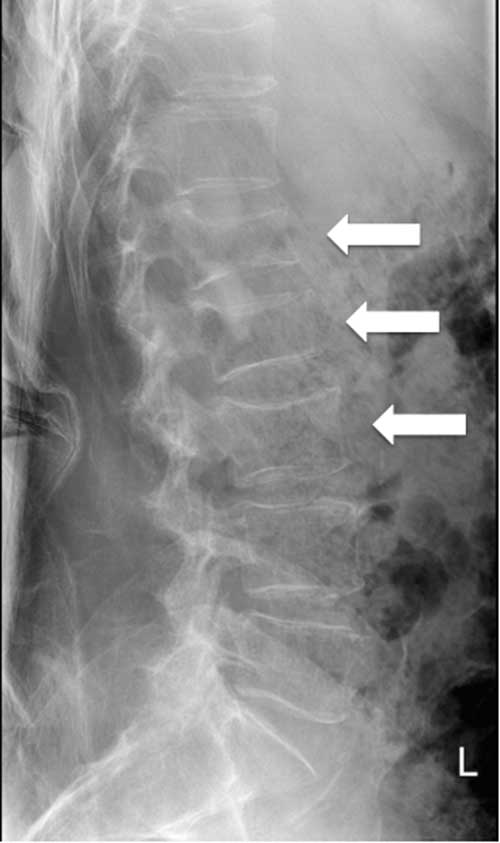

Laboratory investigations revealed pancytopenia, with a hemoglobin of 115 (range 137–180) g/L, leukocyte count of 1.9 (range 4.0–11.0×109)/L, and a platelet count of 135 (range 150–400×109)/L. Red blood cells were normocytic with a low reticulocyte count of 1%, and his peripheral blood smear demonstrated rouleaux cell formations. His serum electrolytes and creatinine were within normal limits. Hypercalcemia was detected with a corrected calcium level of 2.80 (range 2.10–2.55) mmol/L. New thoracic and lumbar spinal radiographs revealed subacute compression fractures involving the T11, L1, L2, and L3 vertebrae that were not present on the original films ordered by the family physician (Figure 2).

Figure 2 Lumbar spine radiograph acquired on presentation to the emergency department at 14 days following the initial spinal imaging. Loss of vertebral height of L1 (32%) and L2 (34%) as well as a mild central compression of L3 are revealed.